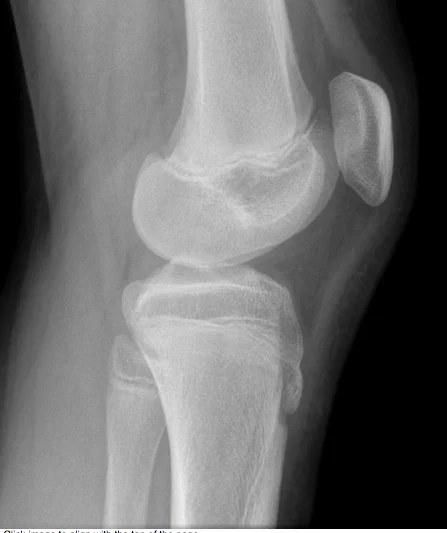

Use Anatomical Description

Annotated Features:

- Diaphysis

- Metaphysis

- Epiphysis

- Growth plate (appears twice)

- Patella or Sesamoid bone (bone inside a tendon)

- Apophysis (normal)

Additional Notes:

- If there was calcification in a specific area, itâs called Fabella.